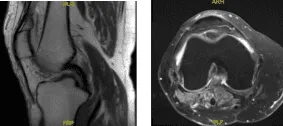

MRI results showed moderate popliteal cyst. Mild lateral patellar subluxation. Medial meniscus tear, new compared to the August 2016 MR study. Chondromalacia as detailed below. Subchondral marrow signal changes associated with patellar chondromalacia have resolved since the previous study.

MRI – 3T Right Knee Non-Contrast